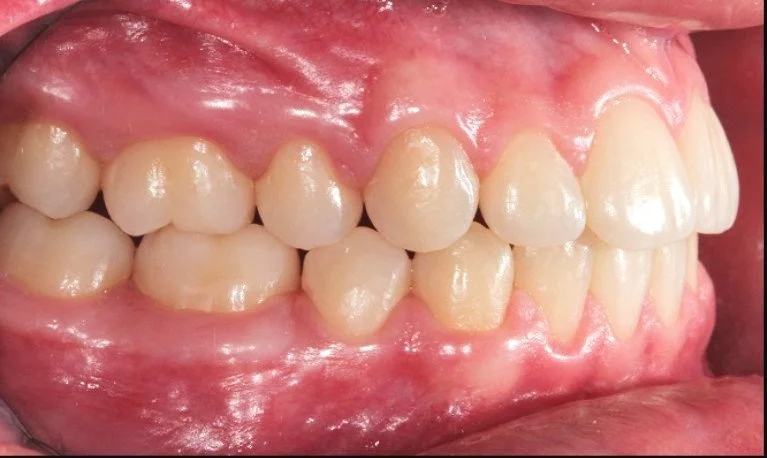

BEFORE

Caso di una paziente con morso aperto iniziale e palato stretto, trattato in giovane età con terapia intercettiva mediante espansione rapida del palato. Successivamente, in adolescenza, è stata sottoposta a trattamento ortodontico fisso in dentatura permanente.